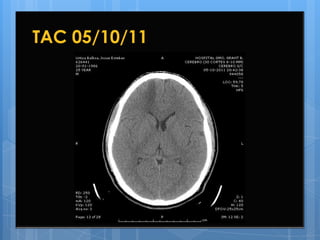

12º Día de Hospitalización

05/10/11

 Estable,  lúcido, afebril, normotenso, hemodiná

micamente estable, no refiere molestias.

Glasgow 15.

 Persiste anosmia.

 Examen físico sin variaciones significativas.

 Se solicita nueva TAC de control.

TAC 05/10/11